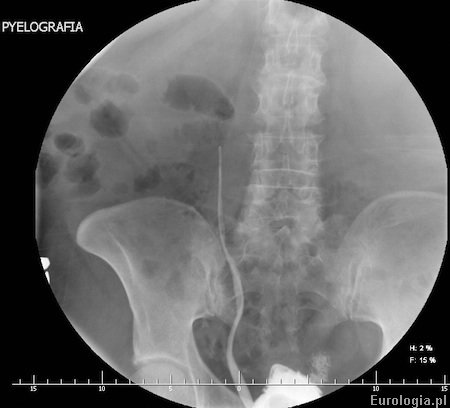

Fot. Pielografia zstępująca

Zdjęcie rentgenowskie powyżej przedstawia obraz pielografii zstępującej po 30 minutach od podania kontrastu przez dren nefrostomijny. Nefrostomia założona była około 3 tygodni wcześniej z powodu prawostronnego roponercza. Stop spływu na wysokości dolnej krawędzi stawu krzyżowo - biodrowego. Przyczyną, która spowodowała roponercze była kamica moczowodowa.